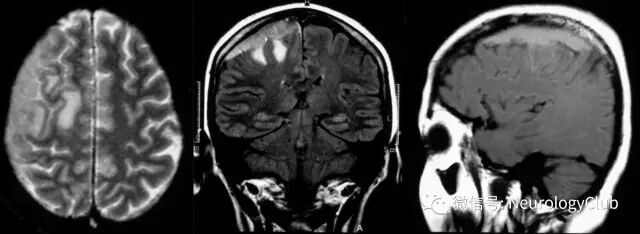

1周后患者接受手术切除,术中发现肿瘤侵犯脑实质和上矢状窦。病理检查提示非典型脑膜瘤(图2)。患者随后接受放疗。

(图2:粉红色和浅褐色组织在高倍镜下可见富于细胞病灶伴中度核异型性;有些区域,细胞呈弥漫片状排列,也可见散在多核巨细胞。亦可见小灶坏死。诊断考虑不典型脑膜瘤。